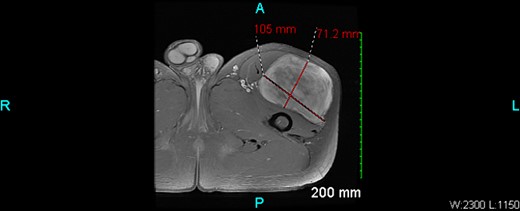

An X-ray of the left femur was negative. An ultrasound revealed abnormal findings, and an MRI with and without IV contrast showed a 10.5 × 7.1 × 11.4 cm heterogeneous enhancing mass within the vastus lateralis muscle without osseous invasion (Figs 1 and 2). There were islands of fat versus hemorrhage within the mass. The overall findings were non-specific but favored a sarcoma.

The case also highlights the importance of imaging in the diagnosis of ASPLT. In this case, an X-ray of the left femur was negative, but an ultrasound revealed abnormal findings, and an MRI showed a heterogenous enhancing mass within the vastus lateralis muscle without osseous invasion. These findings were non-specific but favored a sarcoma [2].